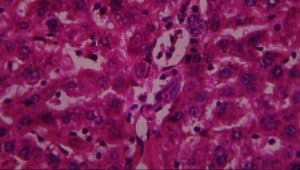

Figure 12: Rat given lead acetate only showing: A-vascular ulceration, B-periportal infiltrates of inflammation, C-vascular congestion and D-necrosis (H&E x 400)

In group III (lead only), the histological evaluation (Figure 6) demonstrated vascular ulceration, vascular congestion, intense necrosis of major liver architecture, and periportal inflammation, further confirming the toxicological effect of lead on the liver. The above histological finding corroborated earlier work done by[26,27,28,29] on vascular congestion of the liver architecture[30] on necrosis of the liver architecture and on the vascular ulceration and periportal inflammation.[31]